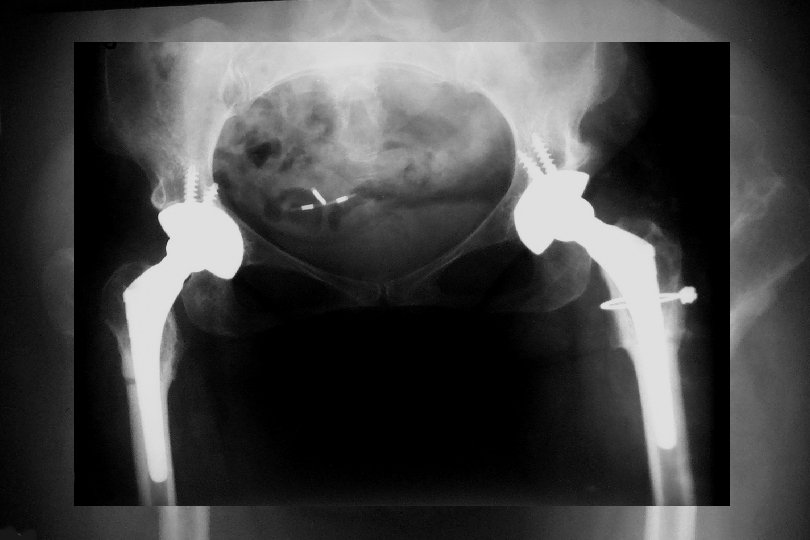

Adult • Artrodez !!! • Total Eklem Replasmanı • Genç ve aktif yaştalar • İyileştirilmiş malzemeler kullanılmalı • Hasta çok detaylı bilgilendirilmeli